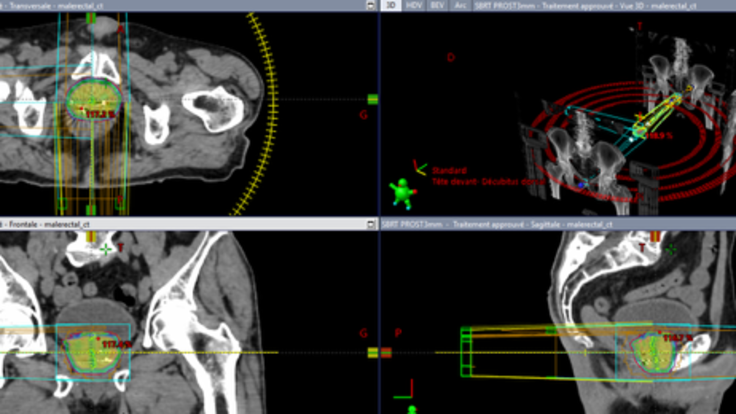

Il s’agit d’une 𝐞́𝐭𝐮𝐝𝐞 𝐝𝐞 𝐩𝐡𝐚𝐬𝐞 𝐈𝐈𝐈 𝐫𝐚𝐧𝐝𝐨𝐦𝐢𝐬𝐞́𝐞 évaluant l’efficacité de l’association 𝐝𝐚𝐫𝐨𝐥𝐮𝐭𝐚𝐦𝐢𝐝𝐞 et d’un 𝐛𝐨𝐨𝐬𝐭 𝐩𝐫𝐨𝐬𝐭𝐚𝐭𝐢𝐪𝐮𝐞 𝐞𝐧 𝐫𝐚𝐝𝐢𝐨𝐭𝐡𝐞́𝐫𝐚𝐩𝐢𝐞 𝐬𝐭𝐞́𝐫𝐞́𝐨𝐭𝐚𝐱𝐢𝐪𝐮𝐞, chez des patients atteints d’un 𝐜𝐚𝐧𝐜𝐞𝐫 𝐥𝐨𝐜𝐚𝐥𝐢𝐬𝐞́ 𝐝𝐞 𝐥𝐚 𝐩𝐫𝐨𝐬𝐭𝐚𝐭𝐞 𝐚̀ 𝐡𝐚𝐮𝐭 𝐫𝐢𝐬𝐪𝐮𝐞 𝐝𝐞 𝐫𝐞𝐜𝐡𝐮𝐭𝐞.